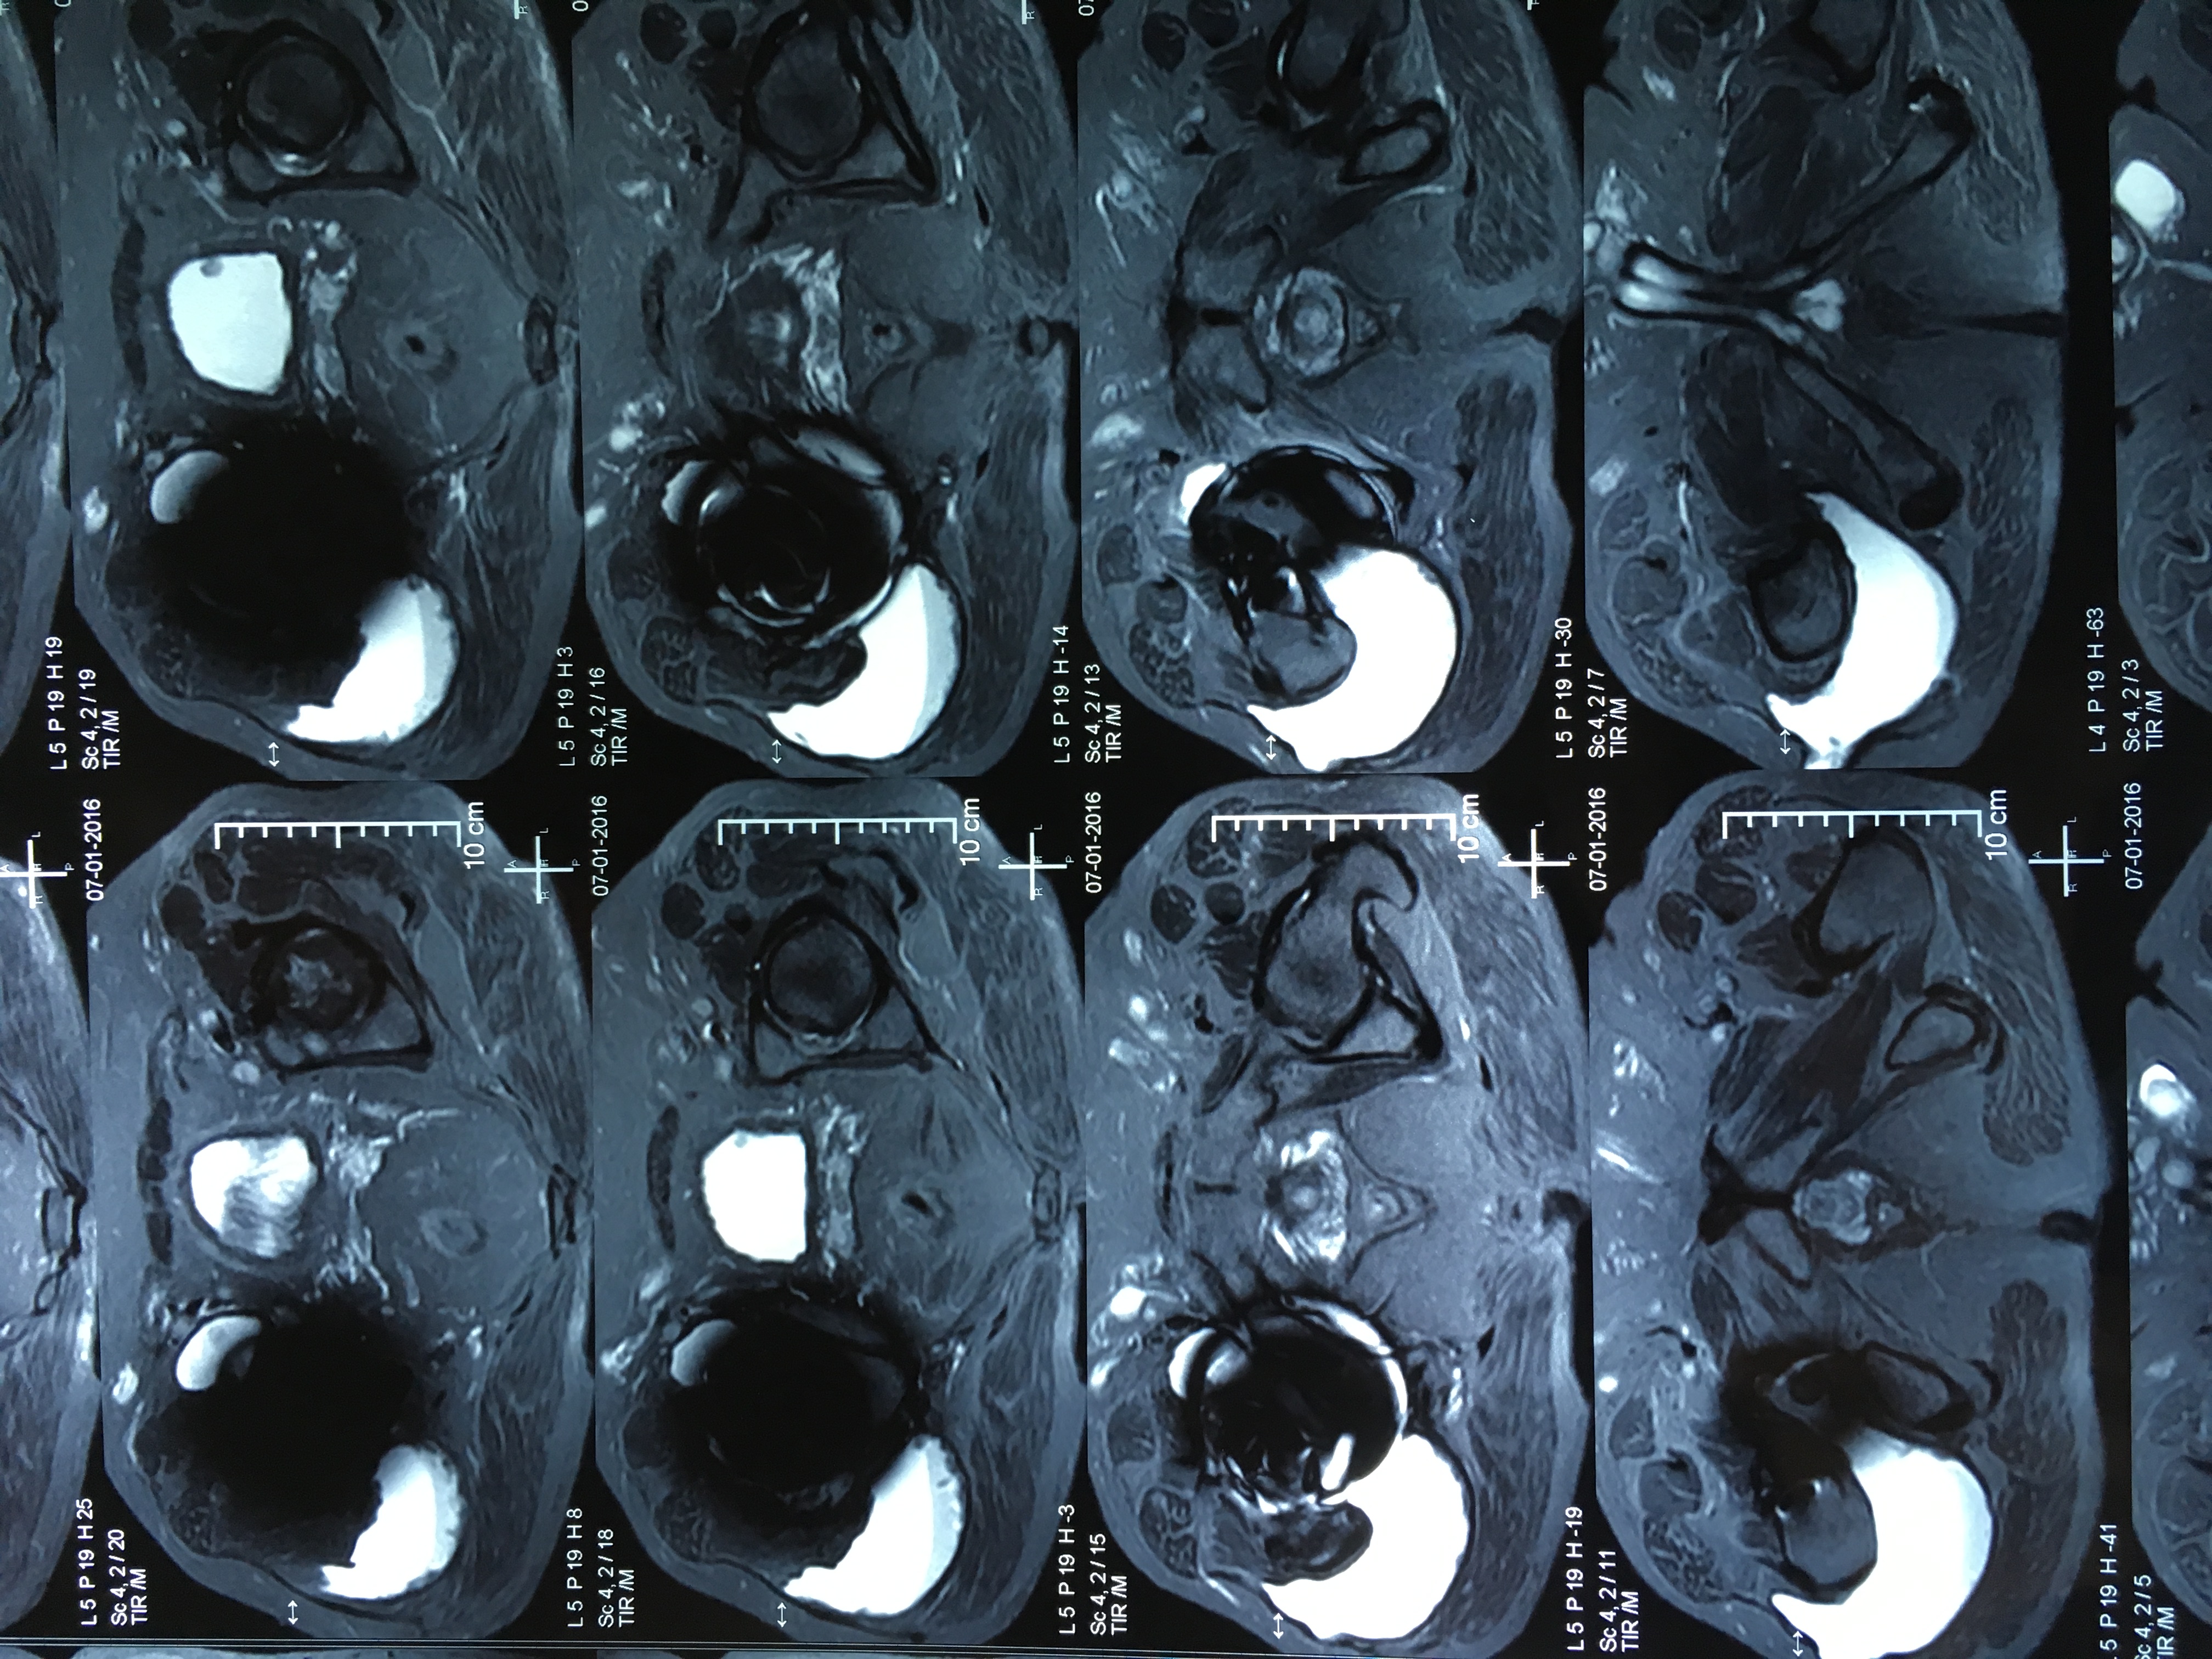

Cotilos de doble movilidad. Uso para la revisión femoral aislada de prótesis de cadera con fricción metal/metal con cabezas grandes. [Use of dual mobility acetabular cups for isolated femoral revision of metal on metal hip resurfacing arthroplasty using larger femoral heads]